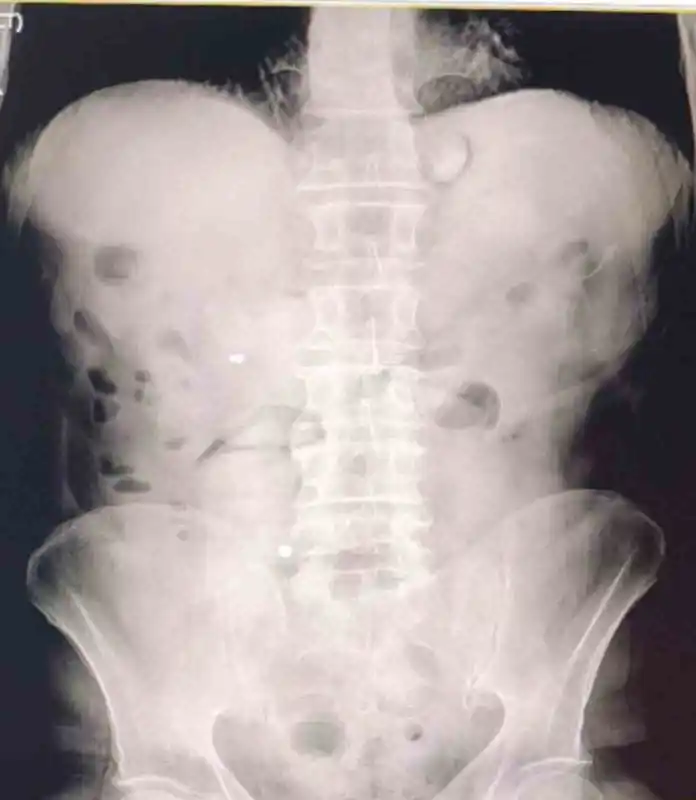

Şüphelilerin hastanede yapılan kontrolleri ve çekilen röntgen filmleri, mide ve bağırsaklarında çok sayıda uyuşturucu madde içeren kapsül olduğunu ortaya koydu. Şüpheliler hastanede kontrollü şekilde gözetim altına alındı.

93 Kapsül Halinde Ele Geçirilen Metamfetamin

Yapılan tıbbi müdahaleler neticesinde şüphelilerden toplam 93 parça halinde 1 kilo 70 gram metamfetamin ele geçirildi. Maddenin vücut içinde kapsüller halinde taşındığı tespit edildi.